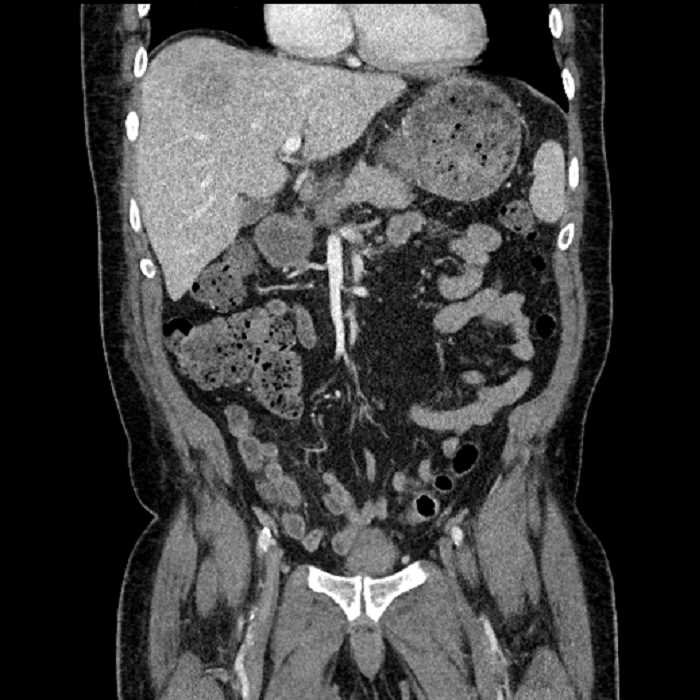

Age: 63

Sex: Male

Indication: Abdominal pain

• Large fluid density structure in hepatic segments 7 and 8 measuring 10 x 7 x 7 cm with internal septation and circumferential ill-defined low density compatible with edema

• Peripherally enhancing subcapsular collections along the anterior margin of the left hepatic lobe measuring 3 x 1 cm and 2 x 1 cm

• Clearly marginated fluid density structure in segment 7 and several other scattered tiny hypodensities, which likely represent cysts

• Hepatic abscess

Acute sigmoid diverticulitis complicated by a small contained perforation and a large abscess in the right hepatic lobe. Additional small subcapsular abscesses along the anterior margin of the left hepatic lobe.

• The classic CT imaging appearance is a double target sign with internal low density surrounded by an internal enhancing rim (capsule) and a low density external rim (edema)

• Abscesses may be unilocular or multilocular

• Gas is present in a minority of cases

Hepatic abscess showing the double target sign with low density internally surrounded by a thin inner enhancing rim (red arrow) and ill-defined outer low density rim (yellow arrow). Blue arrow indicates an internal septation. Red arrows: additional smaller subcapsular abscesses. Red arrow: focal contained perforation associated with diverticulitis.